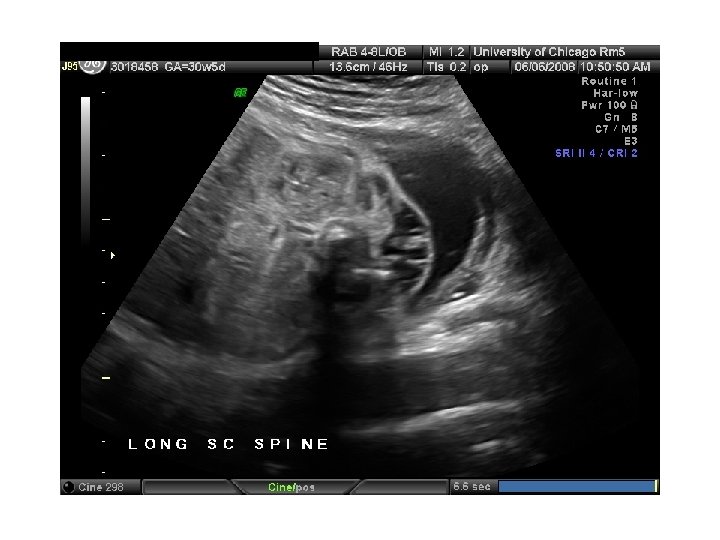

QUIZ What is Your Diagnosis? Case: Patient J. F. 30 years old, at 32 week gestation. Presented with the following pictures.

Answer: a) Trisomy 21 b) Non-immune Hydops c) Paravo virus Infection